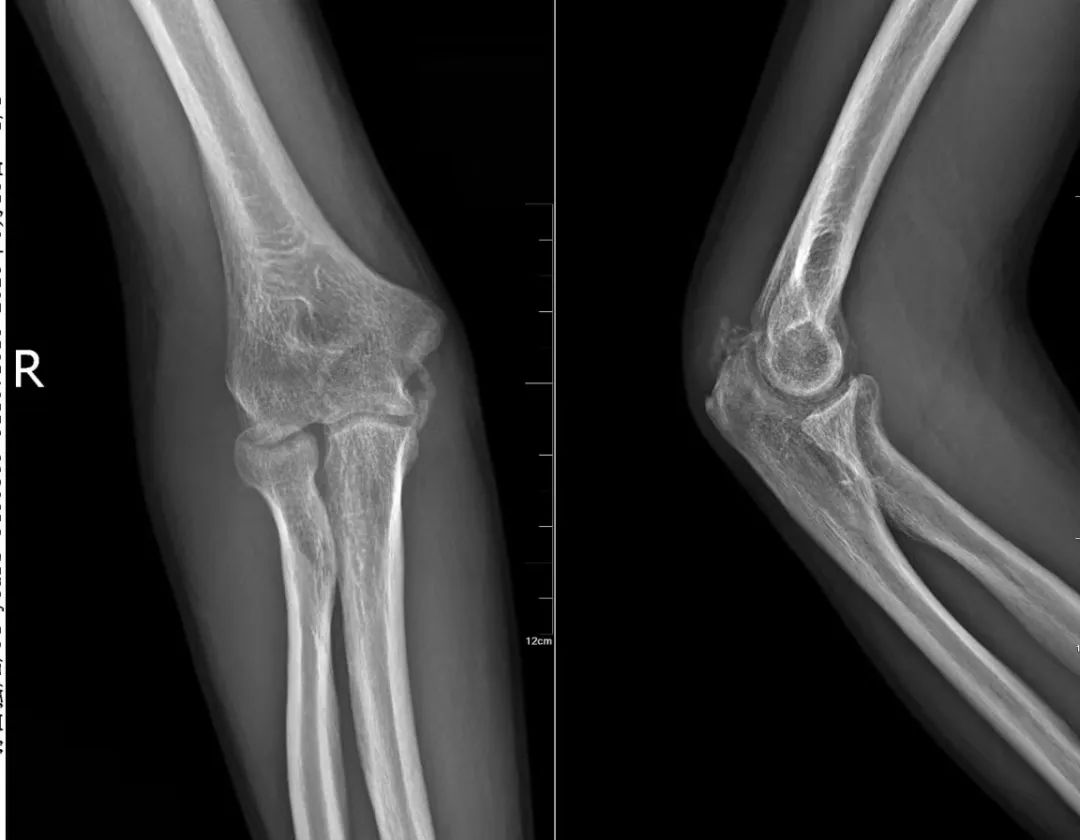

34岁的孙先生对此深有体会:半年前一次摔伤导致右侧桡骨头骨折,在当地医院石膏固定3周后,右肘关节竟逐渐“冻结”,伸屈旋转严重受限。虽经康复治疗,改善甚微。

多方求医后,孙先生找到国内肩肘外科领域专家、北京积水潭医院郑州医院执行院长查晔军。经详细检查,确诊为“创伤后肘关节僵硬”。

考虑到孙先生僵硬的严重程度和病程已达6个月,院长查晔军团队决定施行关节镜辅助下微创肘关节松解术。

肘关节结构复杂,神经血管密布如“雷区”,关节间隙极为狭小,这使肘关节镜手术成为骨科领域极具挑战性的精细操作。